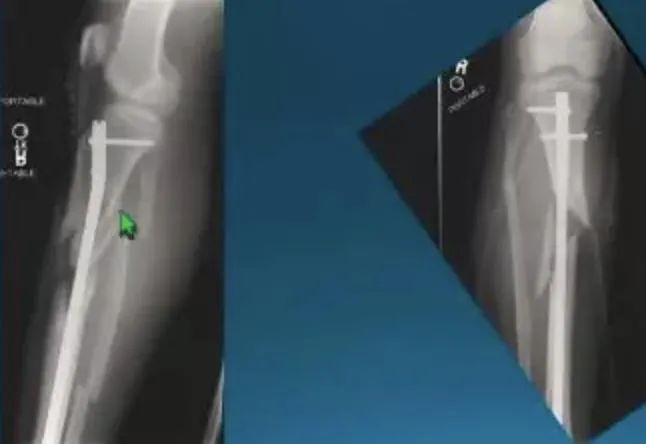

Боль после интрамедуллярного остеосинтеза большеберцовой кости, особенно боль в передней части колена, также распространена.Однако вопрос о том, полезно ли удаление интрамедуллярного стержня для облегчения боли, остается открытым.Боль возникает по многим причинам, включая нарушение нормальных анатомических структур (поднадколенниковая ветвь подкожного нерва, сухожилие надколенника, поднадколенниковая жировая ткань, медиальный мениск и большеберцовое плато или хрящ надколенника) во время введения винта.Однако все методы, направленные на уменьшение вышеперечисленных травм, все же не снижали частоту послеоперационных болей в переднем отделе коленного сустава после применения.Поэтому перед удалением интрамедуллярного стержня врач должен обсудить с пациентом, что хирургическая процедура может не облегчить боль и создать новые послеоперационные осложнения.Боль в передней части колена также может быть вызвана выступающим шипом в точке входа.Артроскопия подтвердила, что выступающий хвост булавки задел суставную поверхность бедренной кости, что привело к повреждению хряща.В то же время выпячивание хвостика ногтя также может привести к повреждению сухожилия надколенника.Показания к удалению интрамедуллярного гвоздя существуют, если доказано, что симптомы или осложнения вызваны грыжей хвостика гвоздя.

Большеберцовый интрамедуллярный стержень: надежное решение при переломах большеберцовой кости